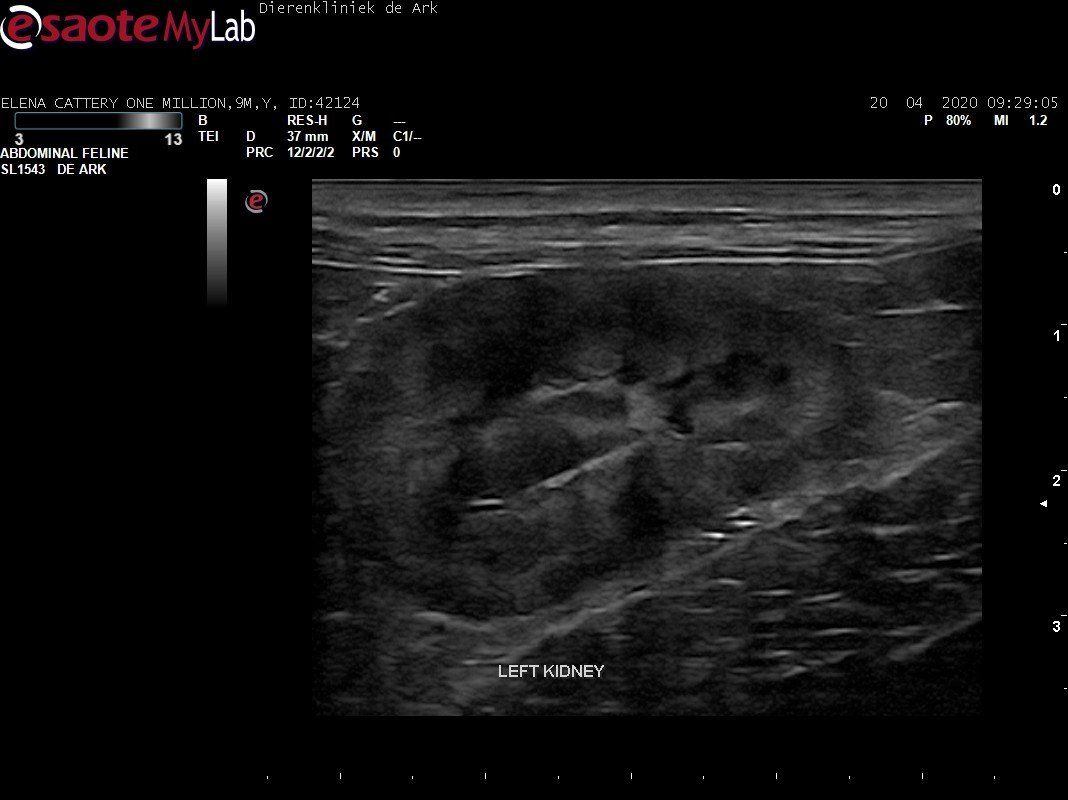

3,200 kg , echo en nieuw bloedonderzoek gedaan wat perfect ging door middel van gapabetine

Voor de garanties en om recht te hebben op medicatie bij herval eist Mutian diverse onderzoeken en controle momenten. Dit zijn bloedonderzoeken maar ook zoals hieronder te zien is echo's. Elana is volledig gecontroleerd op afwijkingen, gelukkig waren de echo's goed.

Ook de bloeduitslagen waren in orde, we kregen groen licht om te stoppen met behandelen en de wachtperiode in te gaan.